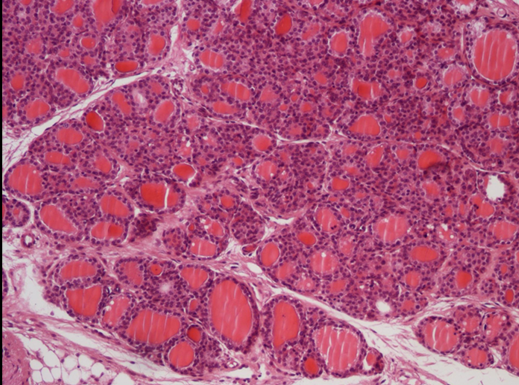

komórki pęcherzykowe = nabłonek jednowarstwowy sześcienny

koloid

komórki C

tarczyca (f. gruczołowa endokrynna nabłonka) nr 408